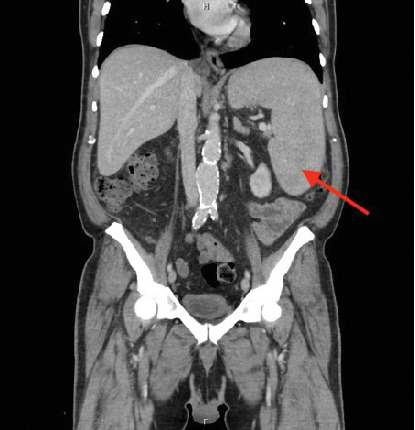

Systemic mastocytosis (SM) is a rare blood disorder characterized by the clonal proliferation of mast cells in tissues. Mast cells release various vasoactive mediators, including histamine, leukotrienes, prostaglandins, platelet-activating factors, and cytokines such as tumor necrosis factor. Clinical manifestations can range from mild itching to severe distributive shock. In some rare cases, mastocytosis is associated with other blood disorders, such as systemic mastocytosis with associated hematologic neoplasm (SM-AHN). Almost all cases of SM exhibit a KIT point mutation. We report a rare case of KIT-negative SM associated with acute myeloid leukemia. Historically, AML has been associated with a poor prognosis, and further research is needed to understand the prognosis of SM associated with AML. In this particular case, the patient underwent induction chemotherapy with azacitidine and venetoclax, and a follow-up bone marrow biopsy showed a reduction in mastocytosis without complete hematologic recovery. The authors aim to present this case as an example of the complex nature of SM and its diverse clinical presentations.